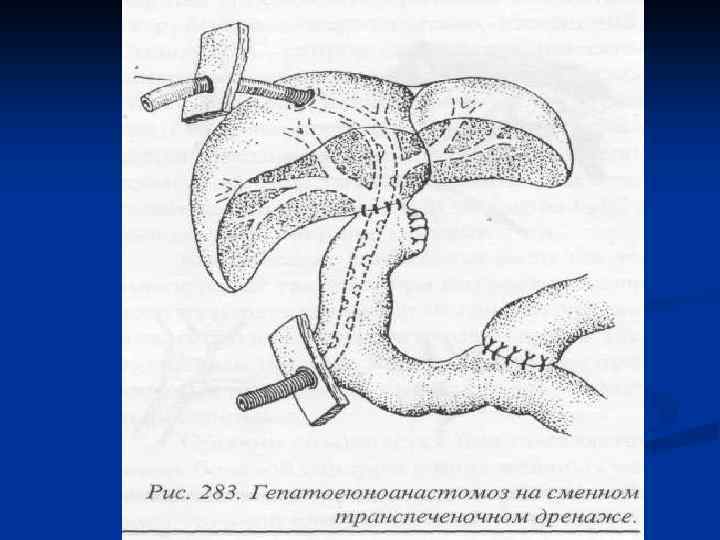

I. Восстановительные операции (восстановление проходимости протоков) 1. Эндобилиарные вмешательства под УЗИ или R – контролем (бужирование, баллонная дилатация, стентирование протоков). 2. Пластика стриктуры 3. Иссечение стриктуры с наложением анастомоза. II. Реконструктивные операции (наложение билиодигестивных анастомозов) 1. Анастомозы внепеченочных желчных протоков: а) с двенадцатиперстной кишкой (ХДА) б) с тощей кишкой (гепатико-, холедохоеюноанастомозы по Ру или по Брауну). 2. Анастомозы внутрипеченочных желчных протоков с сегментом тощей кишки, выключенной по Ру или желудком при высоких стриктурах

I. Восстановительные операции (восстановление проходимости протоков) 1. Эндобилиарные вмешательства под УЗИ или R – контролем (бужирование, баллонная дилатация, стентирование протоков). 2. Пластика стриктуры 3. Иссечение стриктуры с наложением анастомоза. II. Реконструктивные операции (наложение билиодигестивных анастомозов) 1. Анастомозы внепеченочных желчных протоков: а) с двенадцатиперстной кишкой (ХДА) б) с тощей кишкой (гепатико-, холедохоеюноанастомозы по Ру или по Брауну). 2. Анастомозы внутрипеченочных желчных протоков с сегментом тощей кишки, выключенной по Ру или желудком при высоких стриктурах